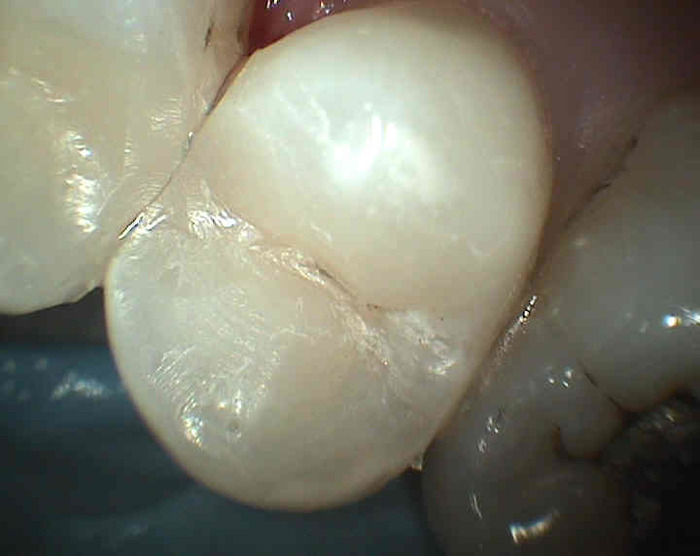

Zubní kaz (caries) je onemocnění způsobené ústní bakteriální flórou a charakterizované rozpadem zubních tkání. Vznikne tehdy, když jsou přítomny zbytky potravy a mikrobi (tedy zubní plak). Nejčastěji vzniká na místech nejhůře přístupných očistě tj. boční stěny zubů ohraničující mezizubní prostor (význam čištění mezizubí !), v rýhách na povrchu zubů, ale také na obnažených zubních kořenech nekrytých sklovinou (zubovina je ke kazu náchylnější z důvodu nižší mineralizace a vyššího obsahu organické hmoty) a na okrajích starých netěsnících výplní.

Příznaky zubního kazu : zdrsnění povrchu zubu, ulpívání zbytků potravy, bolestivost na podráždění (chlad, sladké, někdy při skusu), v mezizubním prostoru se může trhat zubní nit ( ostré okraje kazivé dutiny).